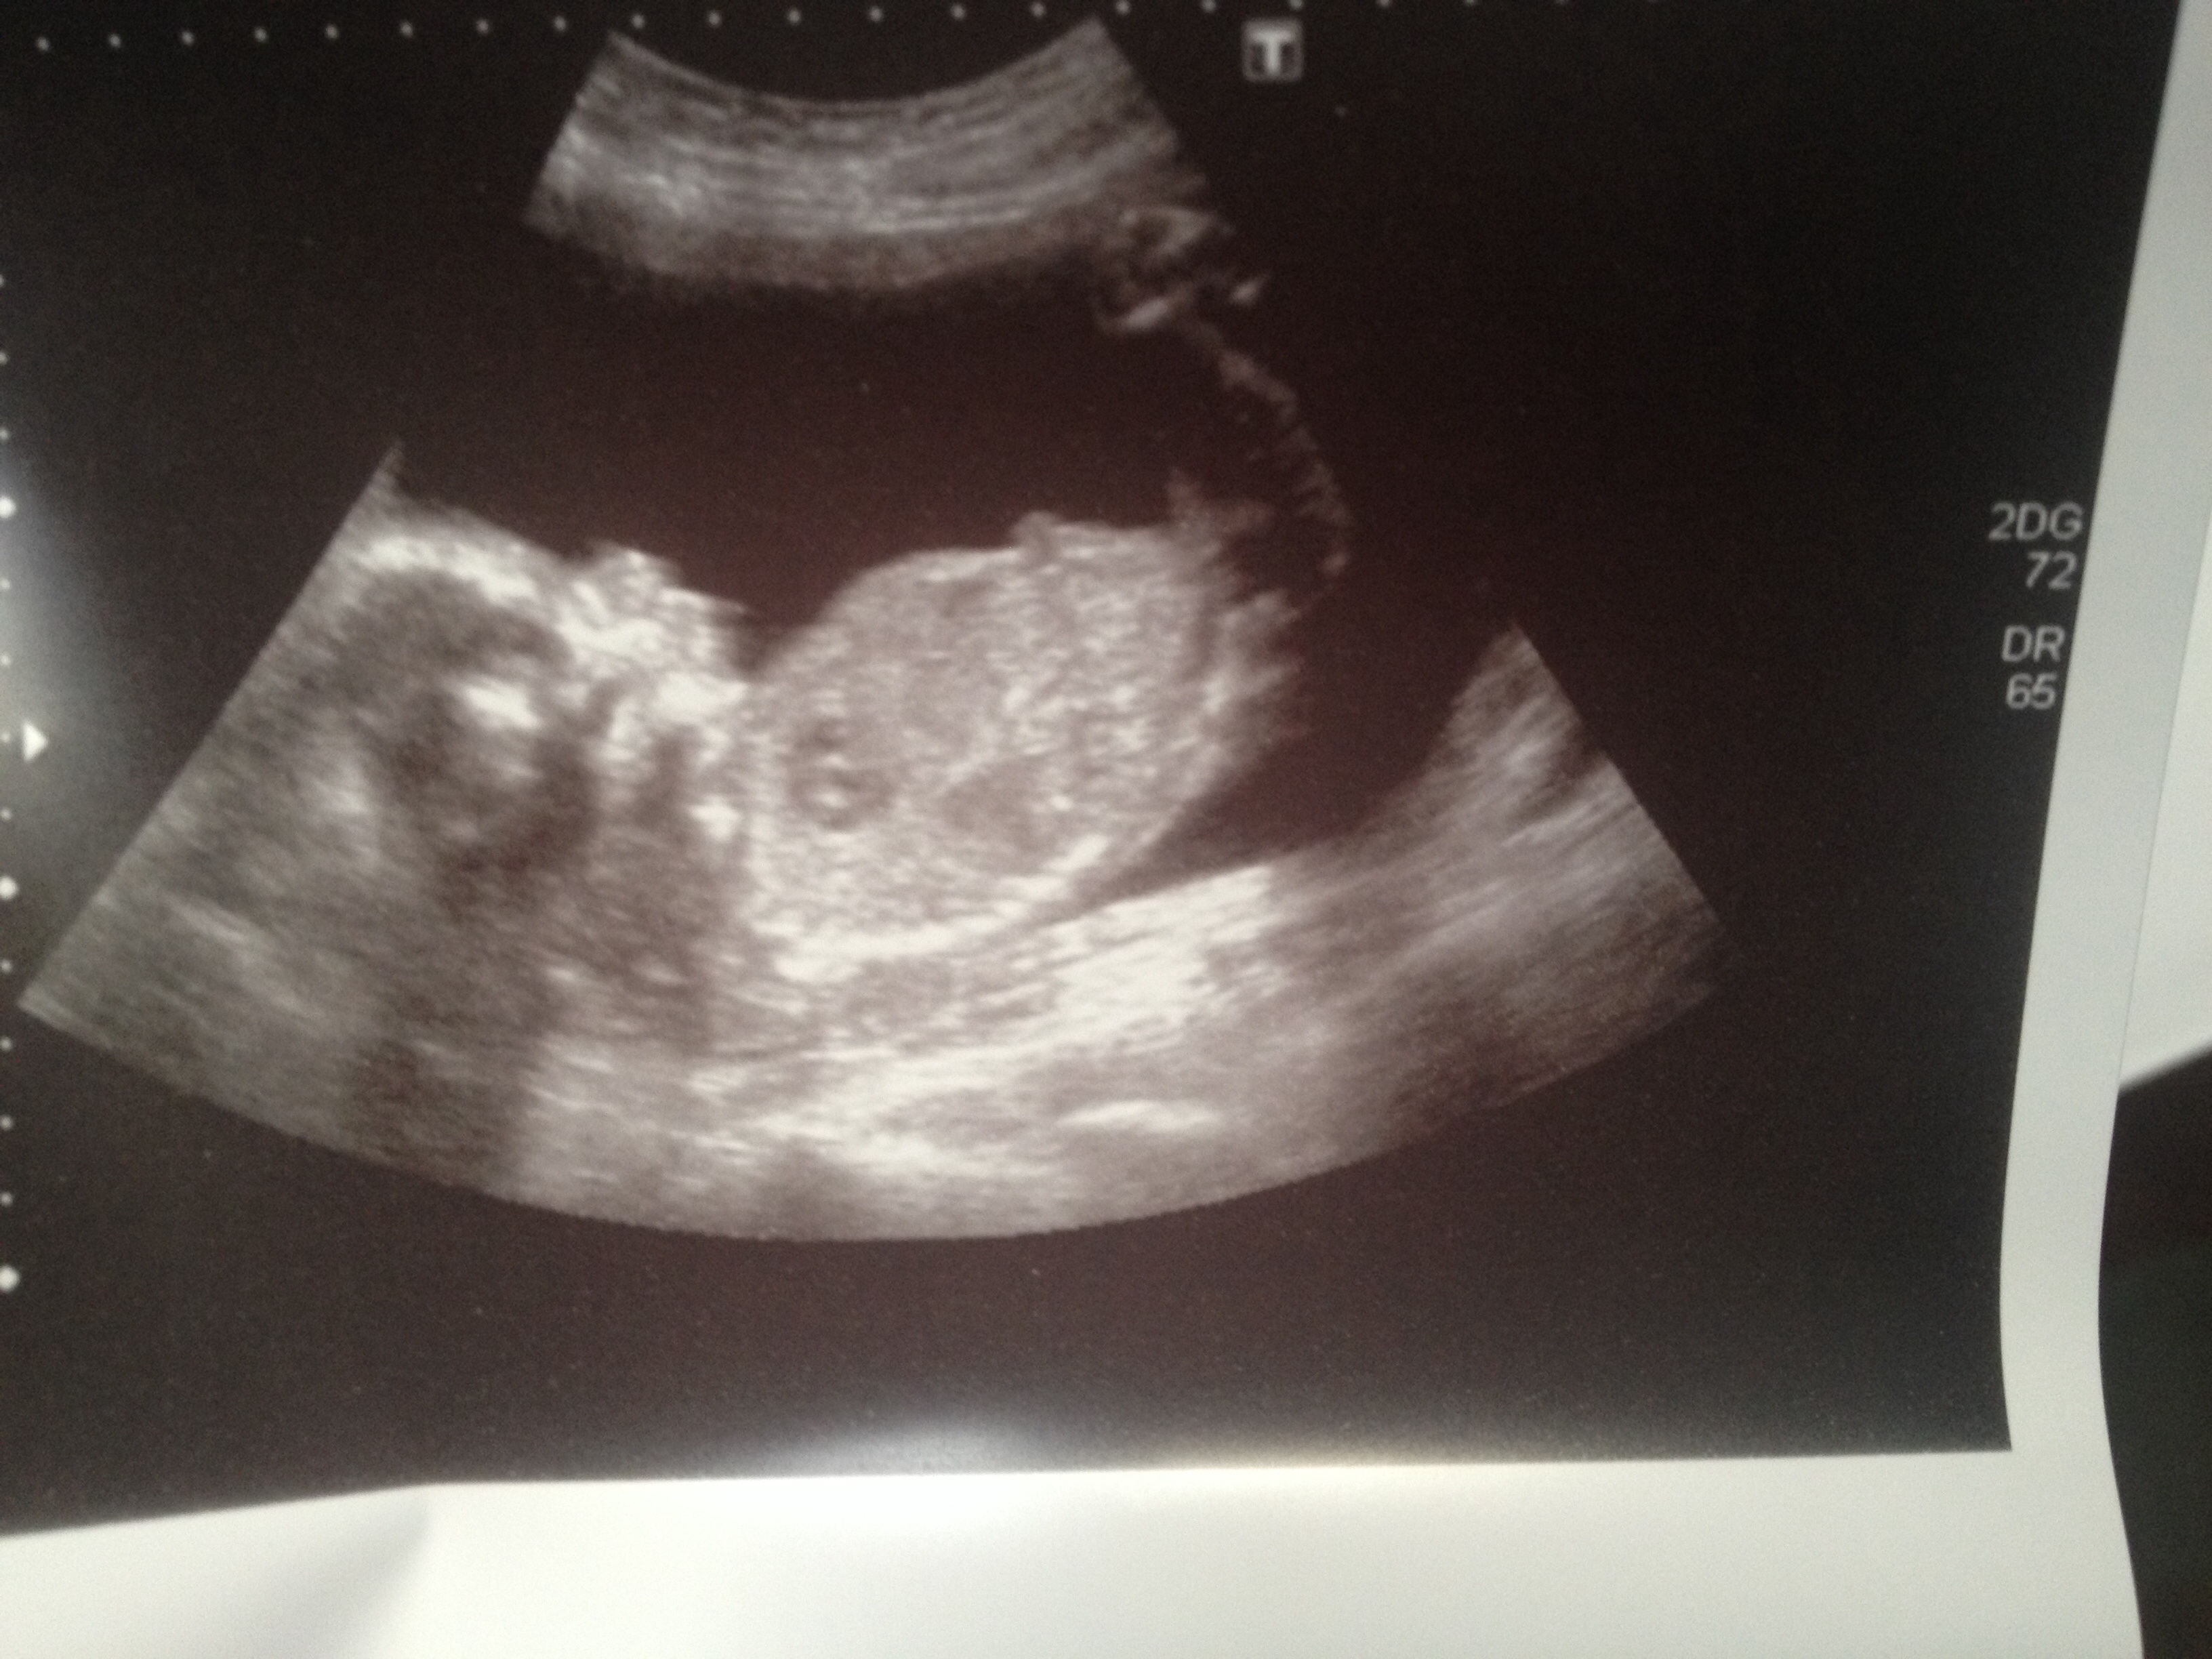

20week scan can any one guess gender please